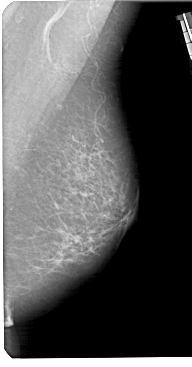

A_1306_1.RIGHT_MLO

RIGHT_CC LINES 5491 PIXELS_PER_LINE 2716 BITS_PER_PIXEL 12 RESOLUTION 43.5 NON_OVERLAY

RIGHT_MLO LINES 5491 PIXELS_PER_LINE 2866 BITS_PER_PIXEL 12 RESOLUTION 43.5 NON_OVERLAY